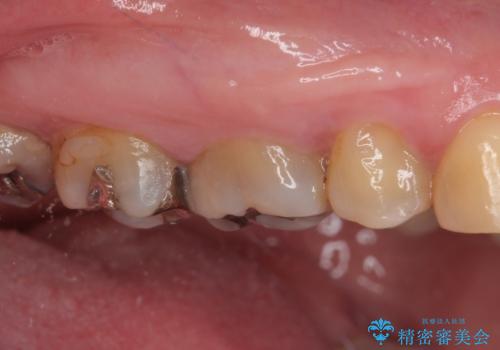

銀歯の下のむし歯 ゴールドクラウンによる補綴治療

- 奥歯で咬んだときに痛みがあり、物が挟まるとのことで来院された患者様です。

咬み合わせが非常に強く、見た目よりも機能と安定性を重視したいとのことで、PGAクラウン(白金加金合金クラウン)にて補綴する治療計画となりました。